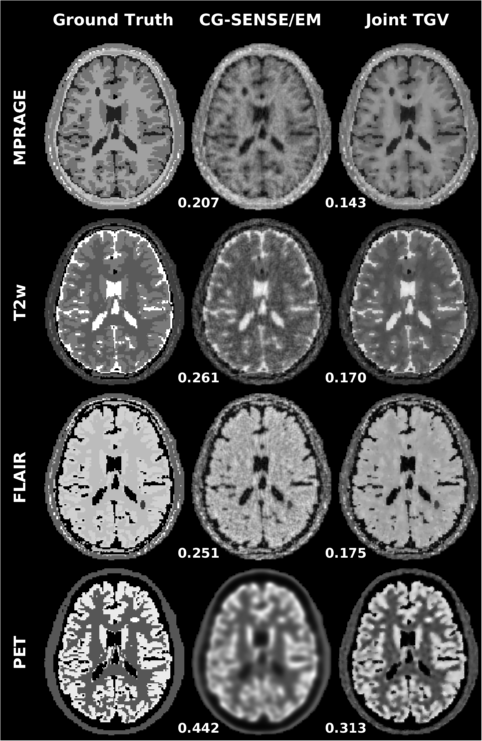

• [46] K. Vunckx, A. Atre, K. Baete, A. Reilhac, C.M. Deroose, K. Van Laere, and J. Nuyts, Evaluation of three MRI-based anatomical priors for quantitative PET brain imaging., IEEE Trans. Med. Imag. 31 (2012), no. 3, 599–612.